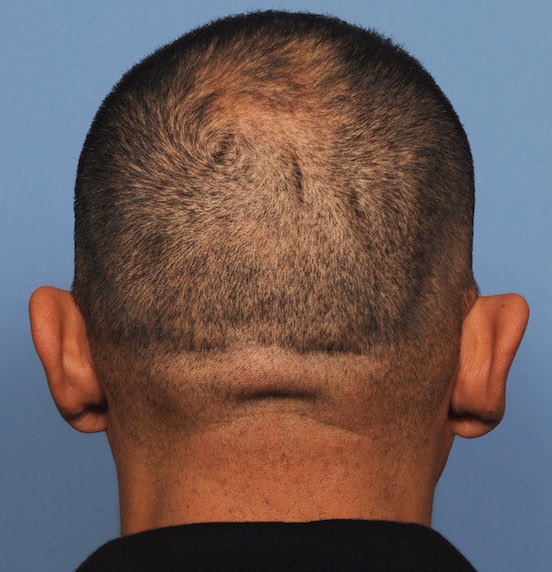

Patient 100

Desire for reshaping of an asymmetric flat back of the head in a shaved head male.

A combined back of the head reshaping procedure was done with a custom skull implant, sagittal ridge reduction and a right temporal muscle reduction.